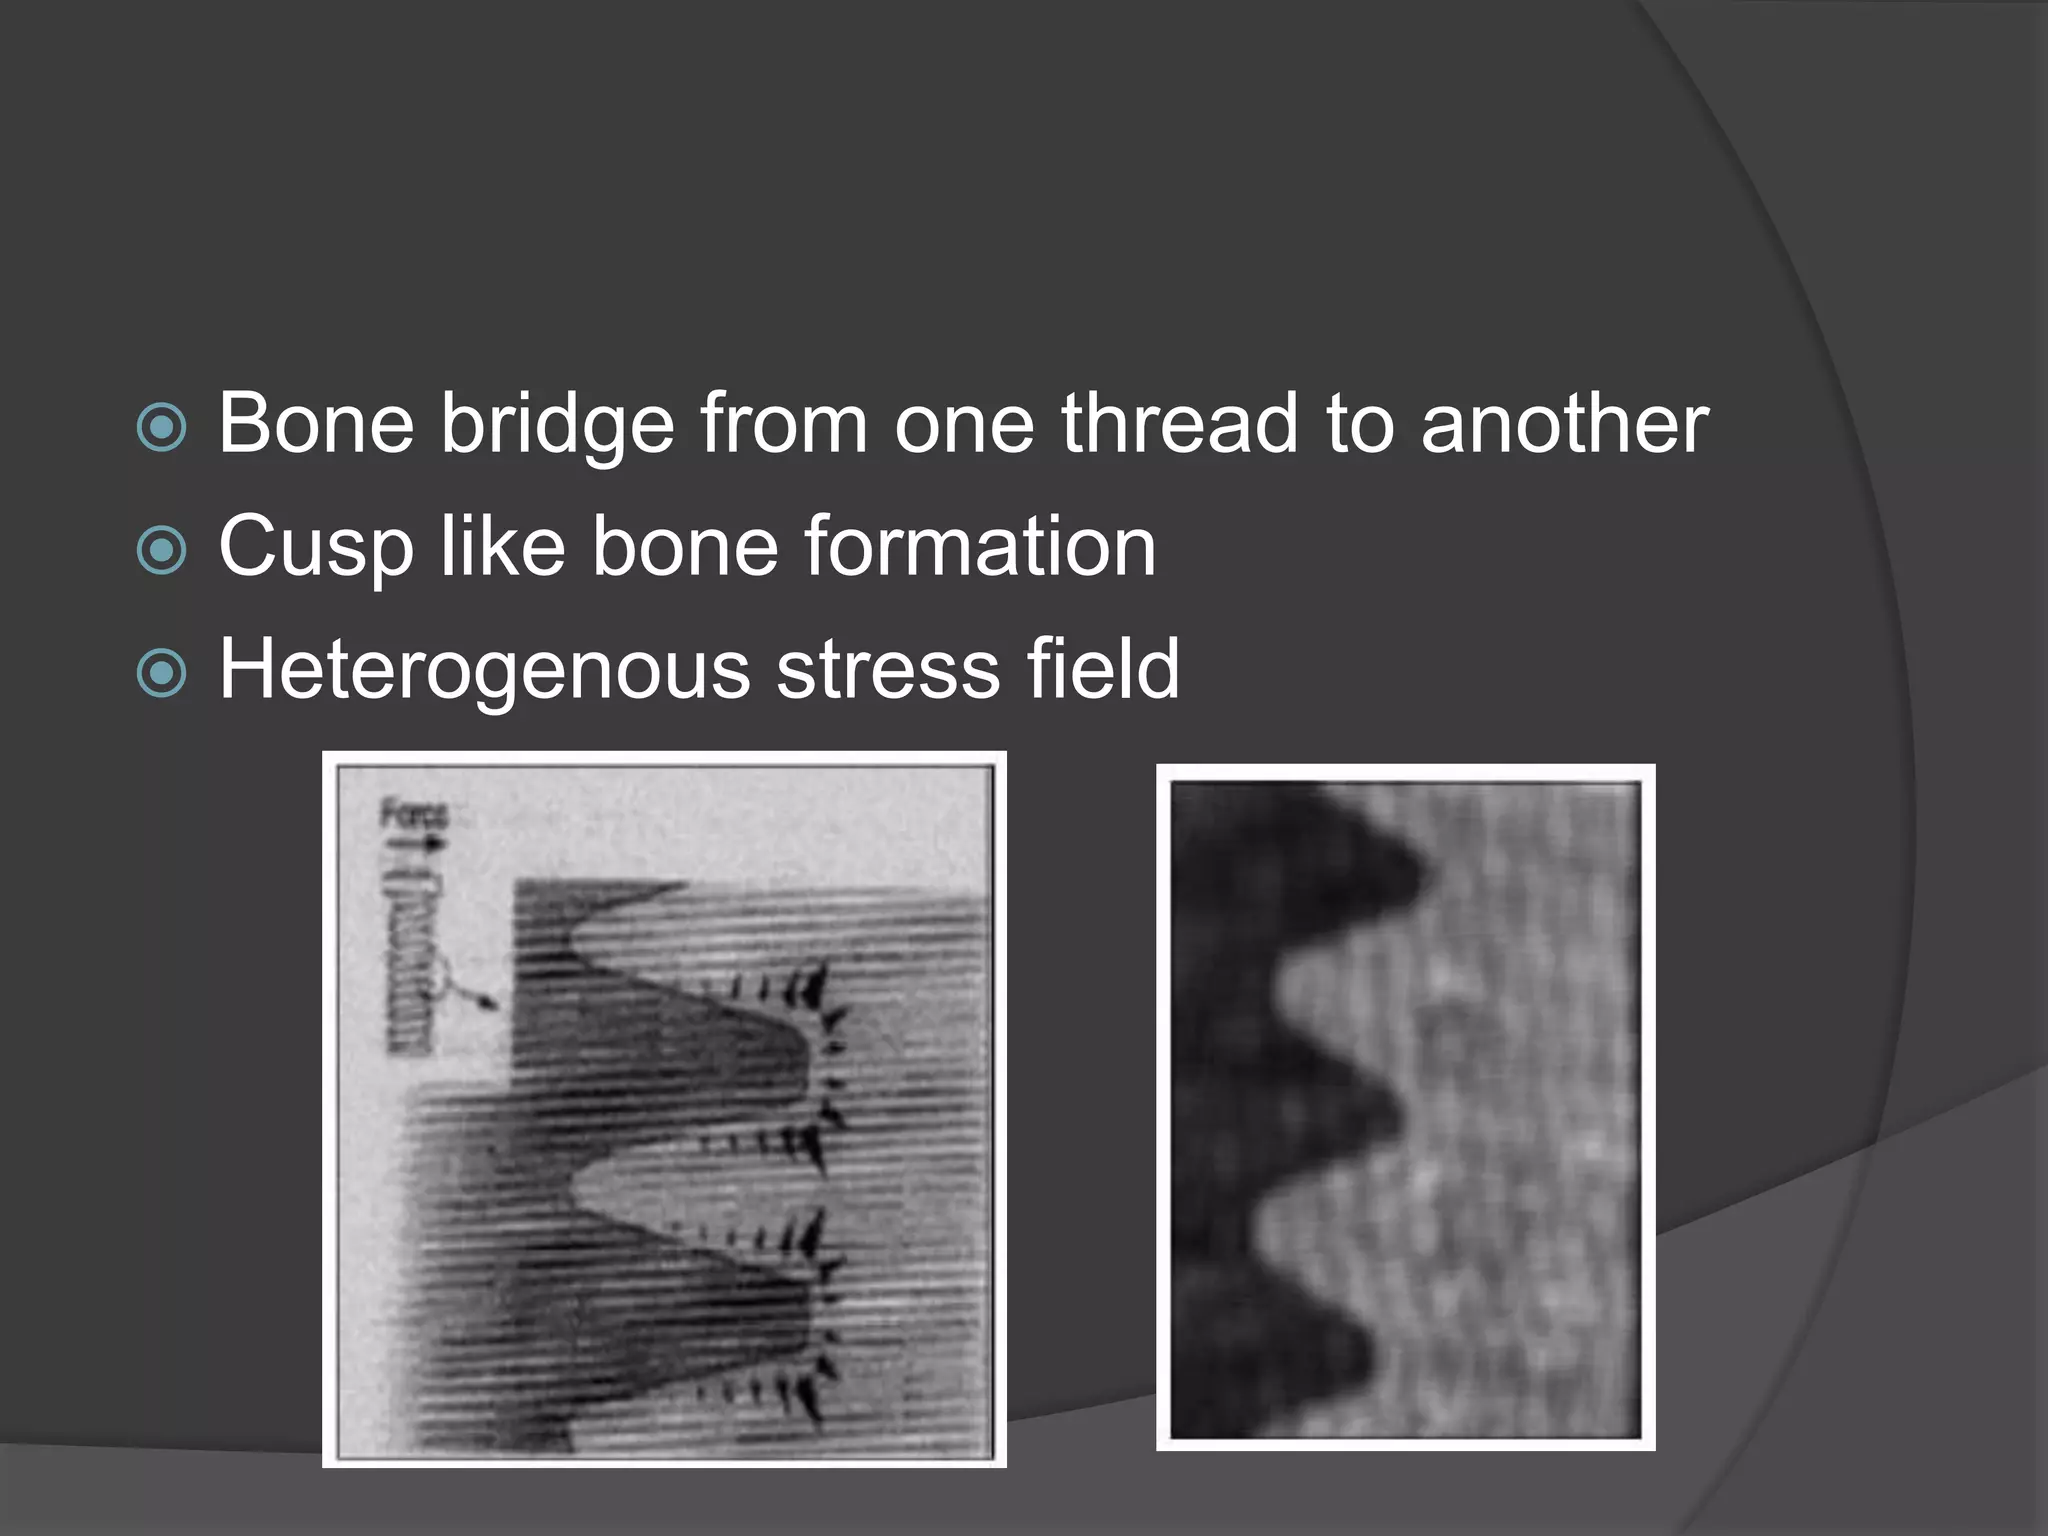

This document discusses factors that influence osseointegration and primary stability of dental implants, including implant design characteristics, surgical technique, and loading protocols. Specifically, it covers the processes of osseointegration and how forces on implants can either promote or inhibit bone remodeling. Key implant design considerations like length, diameter, threads, coatings and surface topography are analyzed in terms of their effects on stress distribution and bone-implant contact. The importance of primary stability and factors influencing it like bone quality and surgical skill are also addressed. Loading protocols ranging from immediate to conventional loading are compared.